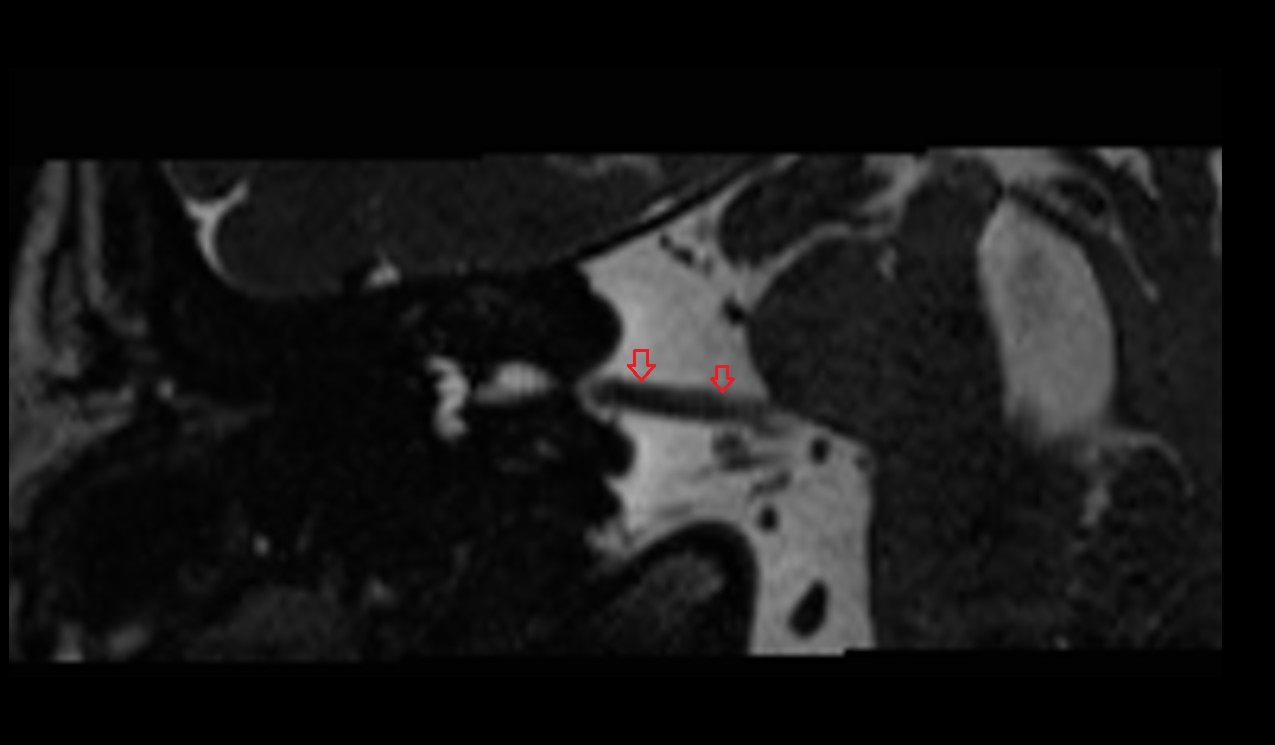

- Temporomandibular joint

- Articular disc of temporomandibular joint

- Intermediate zone of articular disc

- Superior retrodiscal layer

- Superior synovial membrane of temporomandibular joint